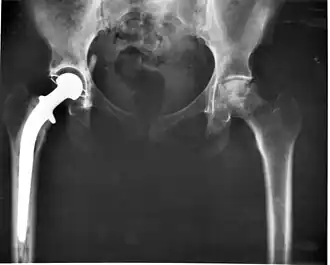

Состояние после эндопротезирования правого тазобедренного сустава. Исход правостороннего коксартроза

Тазобедренный сустав — самый большой и сильно нагруженный сустав. Он состоит из головки бедренной кости, артикулирующей с вогнутой округлой вертлужной впадиной в кости таза. Показаниями к тотальному эндопротезированию тазобедренного сустава (ТЭТБС) являются патологические изменения, вызывающие стойкое нарушение функции с болевым синдромом и контрактурой. Целью тотального эндопротезирования тазобедренного сустава является уменьшение болевого синдрома и восстановление функции сустава. Данная операция является эффективным способом восстановления функции сустава, позволяющий значительно улучшить качество жизни человека. При ТЭТБС заменяется проксимальный отдел бедра и вертлужная впадина. Пораженные участки сустава заменяются на эндопротез, повторяющий анатомическую форму здорового сустава и позволяющий выполнять необходимый объём движений. В вертлужную впадину имплантируется ацетабулярная чашка. B дальнейшем подразумевается остеоинтеграция кости в компоненты протеза. В чашку устанавливается полиэтиленовая или керамическая вставка (оксид алюминия), называемая вкладышем. В бедро имплантируется ножка с конусом на шейке для крепления головки эндопротеза. Головка бывает керамической или выполненной из различных сплавов. Бедренный компонент (ножка) эндопротеза бывает цементной фиксации — и тогда крепится в бедре при помощи специального полимерного материала (костного цемента), а бывает бесцементной фиксации (pressfit) и как правило имеет пористое покрытие для возможности остеоинтеграции кости в компоненты протеза. Цементная фиксация более пригодна для пожилых людей. Различные пары трения (комбинации материалов различных компонентов) имеют различную выживаемость в теле человека. Так, например, самой успешной по выживаемости и самой имплантируемой системой, согласно ведущему независимому источнику Национальному Регистру эндопротезирования суставов Англии, Уэльса, Северной Ирландии и острова Мэн, является бесцементная ножка CORAIL® с бесцементной чашкой PINNACLE® (Johnson&Johnson, DePuy Synthes) c парой трения керамика-полиэтилен. Данная конструкция показывает выживаемость около 98 % за 10 лет наблюдений.

Риск осложнений при имплантации бесцементной ножки CORAIL® с бесцементной чашкой PINNACLE® с разными парами трения также наименьший[14].

Выделяют ряд осложнений — ятрогенный остеомиелит (нагноение), асептическое расшатывание компонентов протеза, различные сосудистые и неврологические нарушения. Нагноение бывает бактериологического плана (стрептококки, стафилококки и т. п.), вирусного (герпес), или грибкового и борются с ним соответствующими средствами — антибиотиками, противовирусными и противогрибковыми препаратами, особенно если конкретную причину удаётся выявить в результате пункций и посевов. При износе эндопротеза его полностью или частично заменяют новым, данная процедура называется ревизионным эндопотезированием сустава.